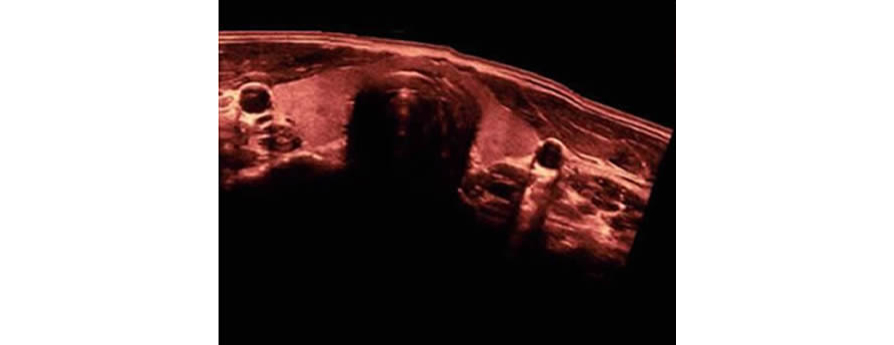

iScape?

Obtenga una vista completa y ampliada de la estructura anatĂłmica con imĂĄgenes panorĂĄmicas que, junto con la indicaciĂłn de velocidad y la capacidad de exploraciĂłn hacia adelante/atrĂĄs, hacen que la exploraciĂłn sea mucho mĂĄs fĂĄcil, mĂĄs suave y mĂĄs controlable.